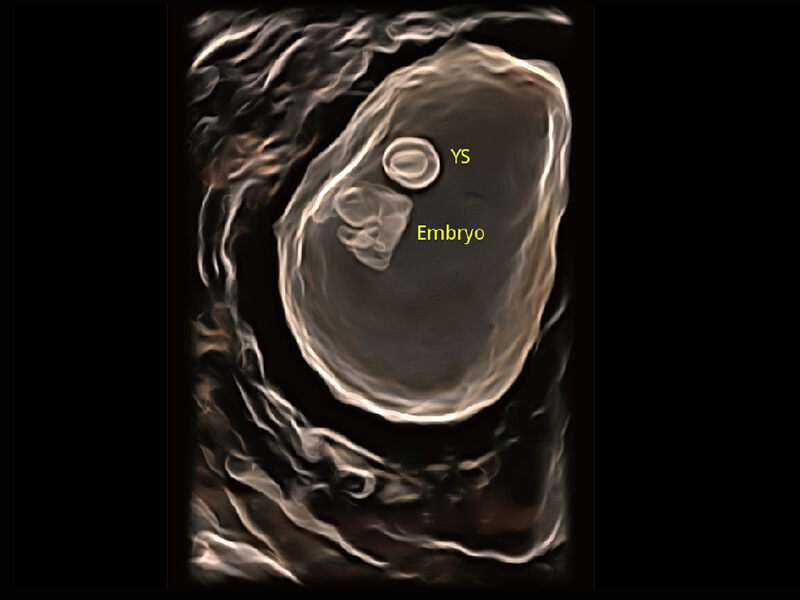

S60探头工艺,从前端信号处理每一个环节采集无损声学数据,真实还原组织原貌,再现解剖细节。

高分辨率容积成像 栩栩如生

超宽频带技术,为容积成像带来优质的二维图像基础,为您呈现丰富的结构细节,栩栩如生地展示宝宝的宫内形态以及各种组织的立体结构。